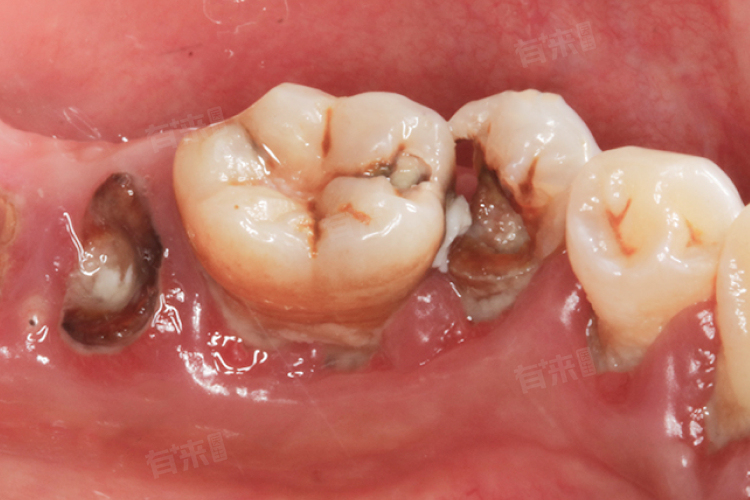

1、牙齿损坏程度加深:蛀牙初期仅破坏牙釉质,若不处理,细菌会持续侵蚀牙体组织,使龋洞逐渐扩大,深入牙本质甚至牙髓,导致牙齿结构被大量破坏,失去原有的形态和功能。

4、影响邻牙健康:蛀牙形成的龋洞内易堆积食物残渣和细菌,这些细菌会蔓延至邻牙,导致邻牙发生龋坏,蛀牙部位的炎症可能扩散,影响周围牙龈组织健康。

- 中龋治疗:龋坏累及牙本质浅层,需彻底清除腐坏组织后,在牙本质表面涂抹保护剂,再进行材料填充,增强牙齿对刺激的抵抗力,治疗后需避免咬硬物,防止填充体脱落。

- 深龋治疗:龋坏接近牙髓,需先判断牙髓状态,若牙髓未受感染,垫底保护后填充;若牙髓受影响,需进行牙髓处理,治疗周期为2-4周,完成后做牙冠修复,对牙齿功能保留较为重要。